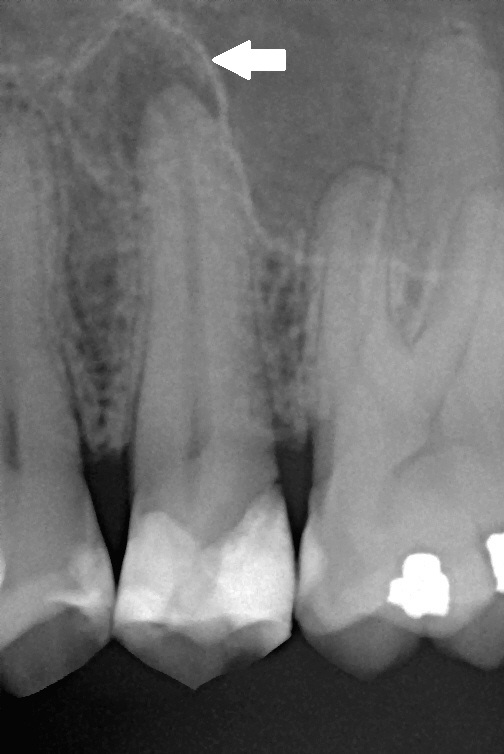

Sur une radiographie retro-alveolaire, un abces peri-apical apparait comme une zone sombre arrondie (radioclaire) au bout de la racine, signe de la destruction osseuse locale. Le traitement necessite de nettoyer le canal infecte (devitalisation ou traitement de canal endodontique) ou d'extraire la dent si elle n'est plus recuperable.